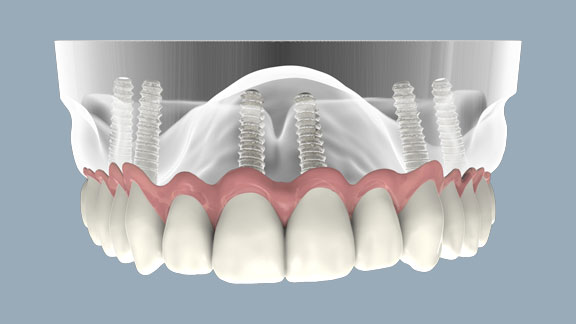

همانطور که می دانید ایمپلنت دندان در یک جلسه انجام می شود و به عنوان جایگزین دندان های از دست رفته می باشد . که پیچی به جنس تیتانیوم داخل استخوان فک به طریق بی حسی موضعی قرار می گیرد و سپس تاج دندان بر روی آن نصب شده و مانند دندان شخص جلوه داده شده و کارکرد دارد ایمپلنت هر دندانی که از دست رفته باشد را پوشش میدهد و قابلیت پوشش یک دندان الی کلیه دندان ها را در بر دارد.

ایمپلنت دندان جلو از اهمیت بسیار بالایی بر خوردار است و نقش حیاتی را ایفا می کند ، زیرا زیبایی دست رفته افراد را به طور طبیعی وتضمینی باز می گردانند . برای ایمپلنت دندان جلویی افراد باید توسط دندانپزشک مورد برسی قرار گیرد تا پارامتر های لازم جهت زیبایی برسی گردد و بافت نگهدارنده ی ایمپلنت به گونه ایی انتخاب گردد که تا آخر عمر سلامت و حجم کافی خود را حفظ کند ، در ایمپلنت دندان جلو زیبایی اطراف ایمپلنت ، سلامت لثه ها ، سلامت دندان های مجاور از اهمیت خاصی بر خور دار است ، به این صورت در انجام آن باید دقت خاصی قائل بود.

این نوع ایمپلنت دندان کاملا دائمی بوده با توجه به این که دندان جلو در معرض آسیب بیشتری قرار می گیرد مقاومت بسیار بالاتری را دارد و اصلا شکسته نمی شود ، از دیگر مزایای ایمپلنت دندان مدت زمان ایمپلنت دندان می باشد که معمولا در دو الی سه جلسه انجام می شود همچنین ایمپلنت دندان زیبایی بخشی آن می باشد زیرا کاملا جلوه ایی طبیعی دارد و زیبایی طبیعی را به افراد هدیه می دهد و چون بیشتر در معرض دید است زیبایی درآن بیشتر اهمیت دارد همچنین این ایمپلنت قابلیت ترمیم شدن را دارد که اگر یک در صد تاج دندان دچار آسیب گردد امکان ترمیم ، جدا سازی و نصب دوباره تاج دندان بر آن را دارد.